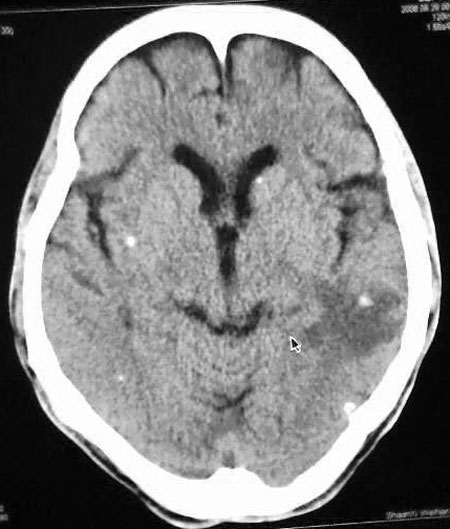

以下是引用守望可可西里在2006-9-6 8:01:00的发言:[br][br] “国内文献进行了脑囊虫病的ct分期:①活动期: ct标志为头节、囊壁、囊液同时存在,分为脑实质小囊型与脑室型;②退变死亡期:ct标志为头节消失、囊腔肿大、虫体崩解,分为单发或多发小囊型、大囊型、葡萄状囊丛型、脑炎型、脑内小脓肿型、脑梗塞型、脑膜炎性③钙化期:标志为囊虫灶转为高密度的钙化结节;④混合期:为活动期、退变期、钙化期病灶混合存在。”[br] 本病例左颞叶、右颞顶叶低密度影,无占位表现,病灶极似脑梗塞。但双侧病灶中偏边缘部位还是有圆形钙化灶,可以考虑为虫体钙化。再加上脑实质内见散在的不对称圆形钙化,其形态类似“大米粒状”,本例应该考虑是脑囊虫病,分期为混合期。